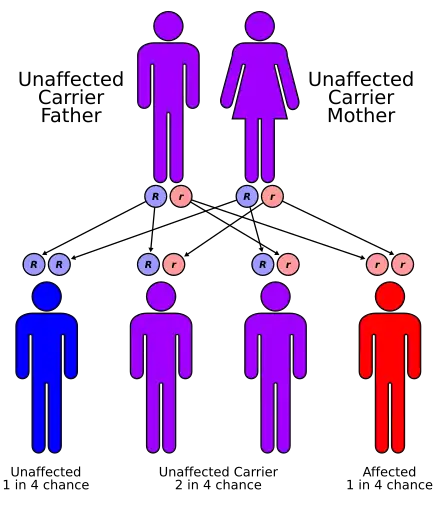

| Very long-chain acyl-coenzyme: A dehydrogenase deficiency has an autosomal recessive pattern of inheritance. | |

VLCAD deficiency is characterized as an inherited genetic disorder. The mutations that occur within the gene itself are recessive, meaning that an individual has to acquire both recessive mutated genes in order for the disease to manifest.[4] There are various forms of the disease that can be manifested in infancy, adolescence, and adulthood.[8] However, it is still unknown at to what causes the disease to manifest itself in the different life stages.